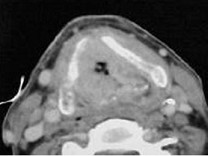

| 男,55岁,声嘶6年,有长期吸烟史。检查:无呼吸困难。喉镜检查:声带慢性充血,可见右侧声带可见菜花样新生物,右侧声带活动固定,喉部CT检查如下图: |

6.诊断首先考虑 ( )![]() ![]() ![]() ![]() |